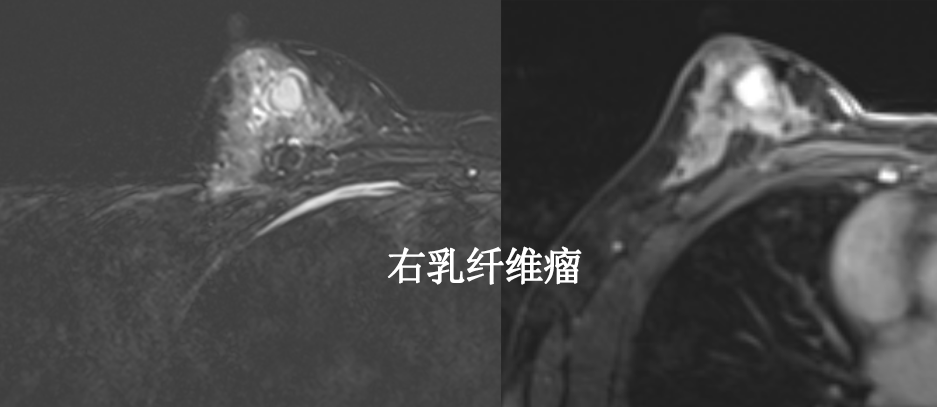

MG/CT:

乳腺炎:包括急、慢性乳腺炎和乳腺脓肿,多见于产后哺乳期妇女,急性乳腺炎常有典型的临床症状-红、肿、热、痛;若治疗不及时可形成慢性乳腺炎或乳腺脓肿。MG 表现片状致密影,边缘模糊,患处皮肤水肿增厚,皮下脂肪层模糊;MRI-T1WI 表现为片状低信号,T2WI 高信号,信号强度不均匀,边缘模糊,皮肤水肿、增厚,增强 MRI 通常表现为轻至中度强化,且以延迟强化为主。